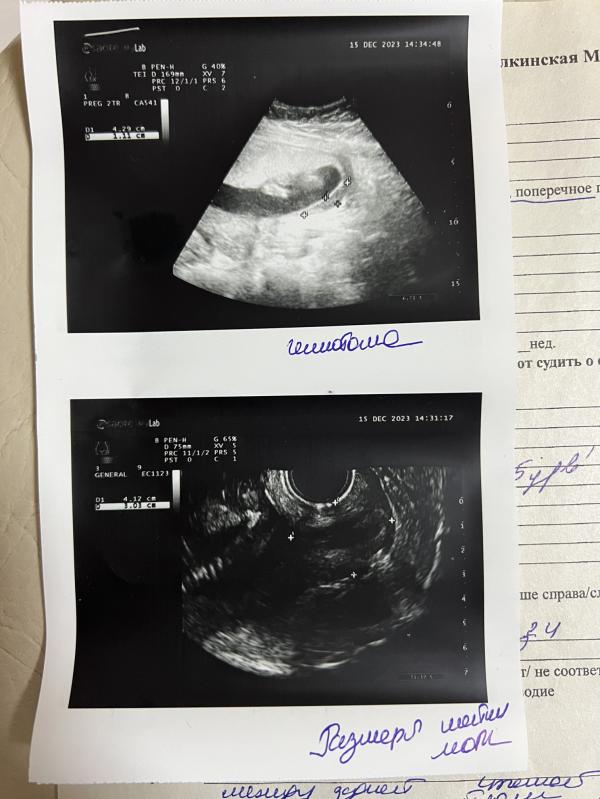

БЛ с 21.11-15.12 гематома была 10,5 *2.2

Сейчас 4,29*1.1, очень надеюсь, что она уйдет ко 2 скринингу.

По узи ребенок врач говорит на 17 недель, срок 16, 2 дня.